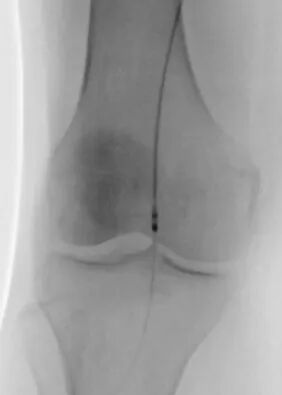

第一个病例中,患者因下肢严重缺血入院。术前常规血管造影提示为“动脉闭塞”。如果按照传统思路,需要直接实施球囊扩张加支架植入手术。为实现精准诊疗,血管外科团队决定启用IVUS进行血管腔内探查。

IVUS探头进入血管后,病变真相清晰呈现。血管内并非预想的慢性动脉硬化斑块,而是大块脱落的血栓堵塞了血管。患者属于急性或亚急性栓塞,与慢性闭塞的治疗方案截然不同,原本的支架方案必须推翻。

术中抽栓正是基于这一精准诊断,团队迅速调整治疗策略,采用Straub-Rotarex血栓切除系统实施精准抽栓治疗。该系统如同血管内的“吸尘器”,能够将血栓碎屑彻底吸出,无需植入支架。

术后患者下肢静息痛即刻消失,血管血流恢复通畅。这一治疗既规避了盲目植入支架可能引发的远期再狭窄风险,也真正做到了“因病施治、精准施策”。